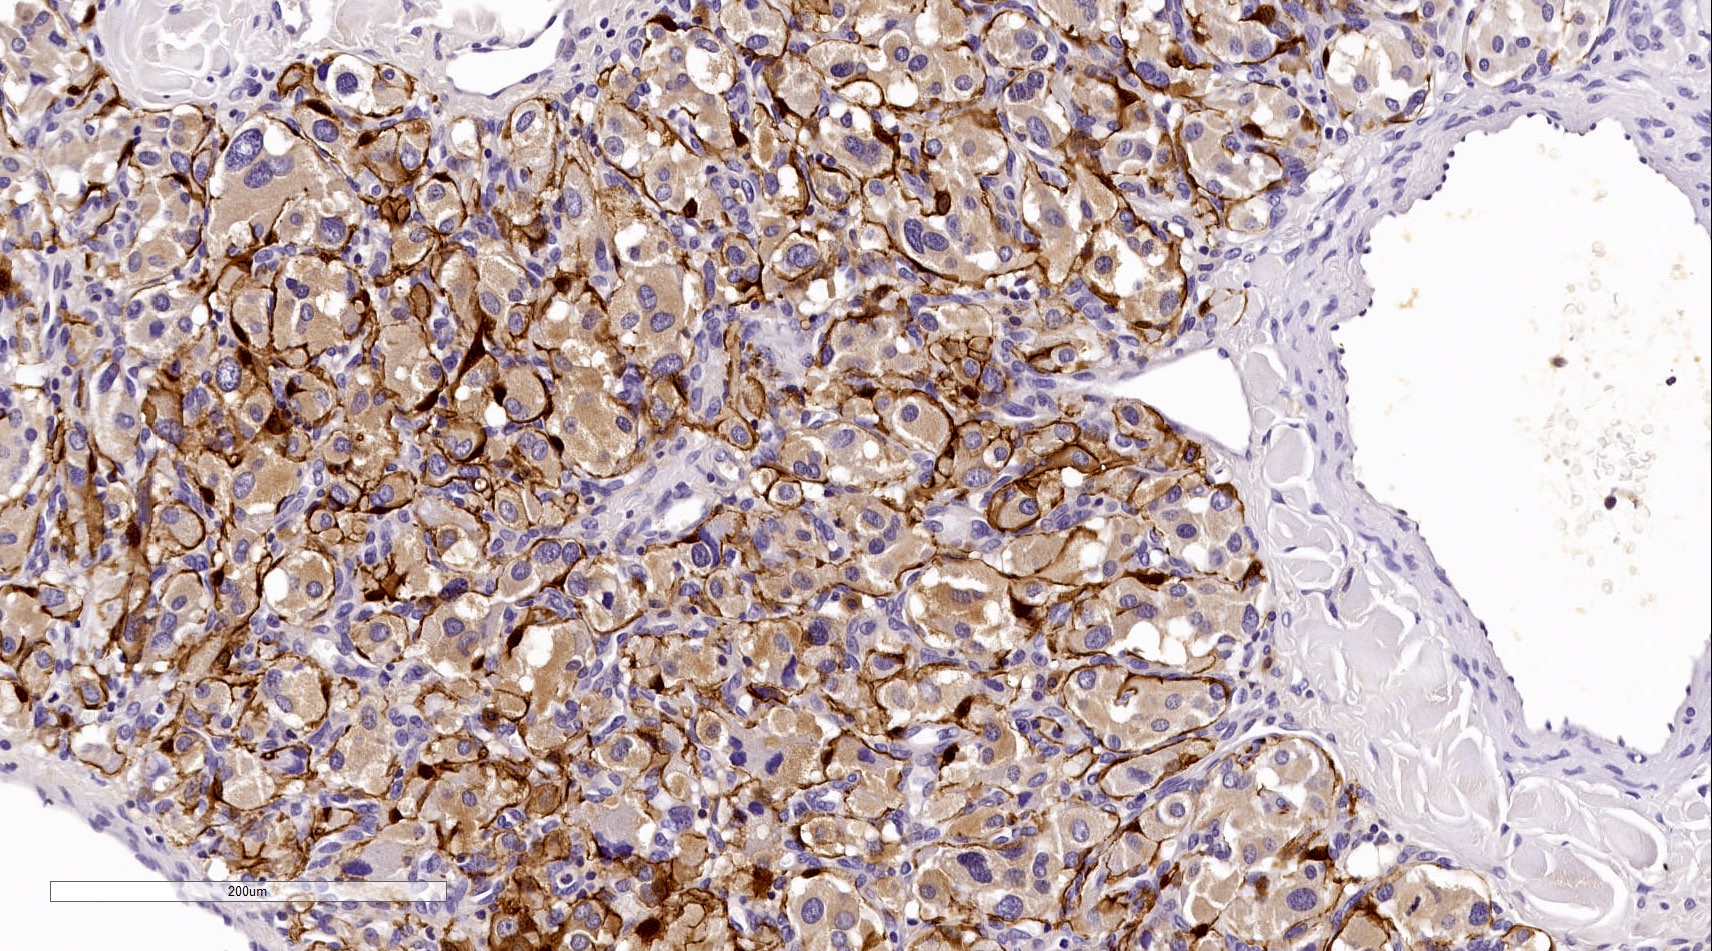

Positive stains

- INSM1 (diffuse nuclear) (Am J Surg Pathol 2018;42:665)

- Chromogranin A (can be only focal or perinuclear dot-like golgi pattern)

- Synaptophysin (Histol Histopathol 1993;8:429)

- CD56 (Endocr Pathol 2002;13:149)

- S100 may be diffusely positive (J BUON 2018;23:1540)

- GATA3 (diffuse nuclear) (Hum Pathol 2020;103:72, Am J Surg Pathol 2014;38:13, J Clin Med 2018;7:280)

- Tyrosine hydroxylase (critical enzyme required for catecholamine synthesis; usually diffuse and strong in sympathetic paragangliomas, may be weak or focal in parasympathetic tumors) (Hum Pathol 2020;103:72)

- Dopamine beta hydroxylase and phenylethanolamine N methyltransferase (PNMT) (epinephrine producing tumors) (see Diagram below) (Neuroendocrinology 2015;101:289, J Clin Med 2018;7:280)

- Sustentacular cells: S100, GFAP and SOX10 (Hum Pathol 2020;103:72)

- IHC surrogate markers for germline mutations:

- SDHB or SDHA expression loss: germline SDHx mutations (Lancet Oncol 2009;10:764)

- FH expression loss: germline FH mutation (HLRCC) (Hum Pathol 2018;71:47)

- Carbonic anhydrase IX (CAIX) expression: 80% of VHL mutation (Mod Pathol 2020;33:57)

- Inhibin alpha: any hypoxic pathway disease (SDHx, VHL, etc.) (Am J Surg Pathol 2021;45:1264)

- Reticulin highlights the nesting pattern (Int J Gynecol Pathol 1991;10:203, Exp Toxicol Pathol 2013;65:631)

Contributed by Luvy Delfin, M.D. and Sylvia L. Asa, M.D., Ph.D.